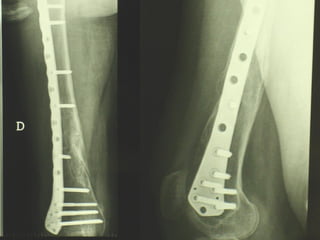

INDICAZIONI COMUNI Fratture sovracondiloidee Fratture intercondiliodee Fratture diafisarie distali PARTICOLARI Fratture con grave osteoporosi Fratture periprotesiche

VANTAGGI CHIRURGIA MININVASIVA Mini Open Inserimento della placca sottocutaneo per scivolamento Viti percutanee Preservazione dei tessuti molli Ridotto danno vascolare Rapida ripresa funzionale

F, 68 y

LISS  NCB

NCB

Conclusioni Riduzione  anatomica Minimo trauma chirurgico Corretto equilibrio fra elasticità e stabilità Precoce mobilizzazione